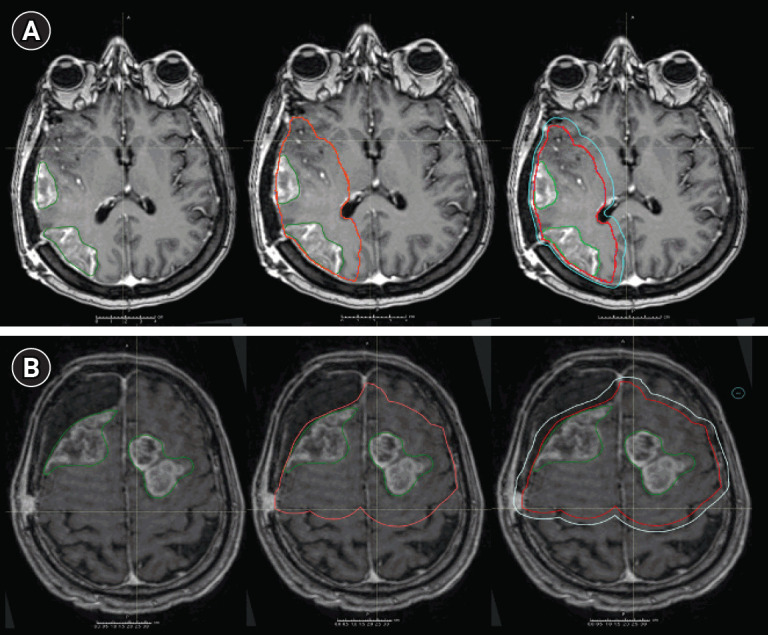

Purpose: No guidelines exist to delineate radiation therapy (RT) targets for the treatment of multiple glioblastoma (mGBM). This study analyzes margins around the gross tumor volume (GTV) to create a clinical target volume (CTV), comparing response parameters and modalities of recurrence. Material and Methods: One-hundred and three mGBM patients with a CTV margin of 2 cm (GTV + 2.0 cm) or 1 cm (GTV + 1.0 cm) were retrospectively analyzed. All patients received a total dose of 59.4-60 Gy in 1.8-2.0 Gy daily fractions, delivered from 4 to 8 weeks after surgery, concomitantly with temozolomide (75 mg/m2). Overall survival (OS) and progression-free survival (PFS) were calculated from the date of surgery until diagnosis of disease progression performed by magnetic resonance imaging and classified as marginal, in-field, or distant, comparing site of progression with dose distribution in RT plan.

Results: OS in mGBM CTV1 group was 11.2 months (95% confidence interval [CI], 10.3-12.1), and 9.2 months in mGBM CTV2 group (95% CI, 9.0-11.3). PFS in mGBM CTV1 group occurred within 8.3 months (95% CI, 7.3-9.3), and 7.3 months in mGBM CTV2 group (95% CI, 6.4-8.1). No difference was observed between the two groups in terms of OS and PFS time distribution. Adjusted to a multivariate Cox risk model, epidermal growth factor receptor amplification resulted a negative prognostic factor for both OS and PFS.

Conclusion: In mGBM, the use of a 1 cm CTV expansion seems feasible as it does not significantly affect oncological outcomes and progression outcome.